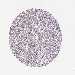

LIVER CANCER - Protein expressioni

A mouse-over function shows sample information and annotation data. Click on an image to view it in a full screen mode. Samples can be filtered based on level of antibody staining by selecting one or several of the following categories: high, medium, low and not detected. The assay and annotation is described here.

Antibody stainingi

Antibody staining in the annotated cell types in the current human tissue is reported as not detected, low, medium, or high, based on conventional immunohistochemistry profiling in selected tissues. This score is based on the combination of the staining intensity and fraction of stained cells.

Each image is clickable and will lead to virtual microscopy that enables deeper exploration of all samples and also displays staining intensity scores, fraction scores and subcellular localization as well as patient and tissue information for each sample.

Antibody HPA053730

Antibody HPA058604

Staining

High

Medium

Low

Not detected

Intensity

Strong

Moderate

Weak

Negative

Quantity

>75%

75%-25%

<25%

None

Location

Nuclear

Cytoplasmic/membranous

Cytoplasmic/membranous,nuclear

Cholangiocarcinoma

Carcinoma, Hepatocellular, NOS